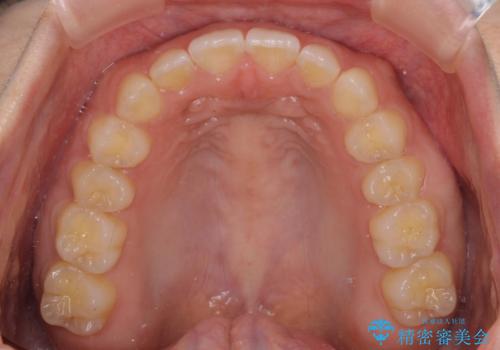

- 後戻りによる上下前歯の隙間を気にして来院された患者様です。

歯列不正はそれほど大きくなかったため、インビザライン・ライトを用いて矯正治療を行うこととしました。

無理のないペースで治療を進め、9ヶ月で終えることができました。